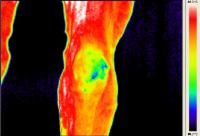

Walzertraum - Pferd nach Sehnen-OP - Horse after tendon operation